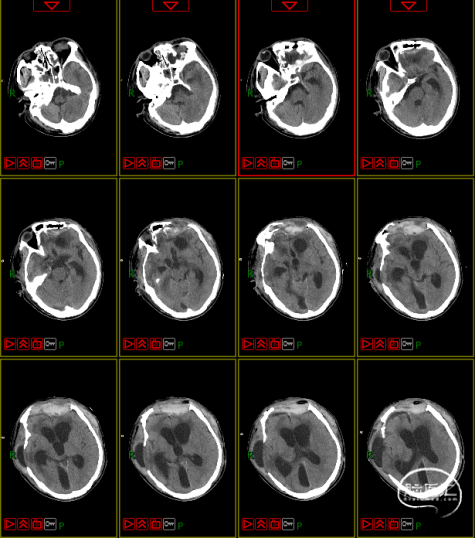

颅骨修补后对颅内压的影响

颅骨修补对颅内压的直接作用:颅骨修补后可恢复颅内压力分布,使得脑组织各个部位受到的压力相对平衡。

颅骨修补对脑组织的影响:颅骨修补使得脑组织重新获得硬质的保护,不易受到外界冲击,同时脑组织的支撑力加强,不易导致脑移位。

颅骨修补对脑脊液循环的影响:颅骨修补可能恢复脑脊液的正常循环,重新恢复脑脊液正常的分泌与吸收。

颅骨修补对血管调节的影响:颅骨修补可在一定程度上恢复脑血管的调节功能,让脑血流量正常,进而恢复颅内压的稳定。